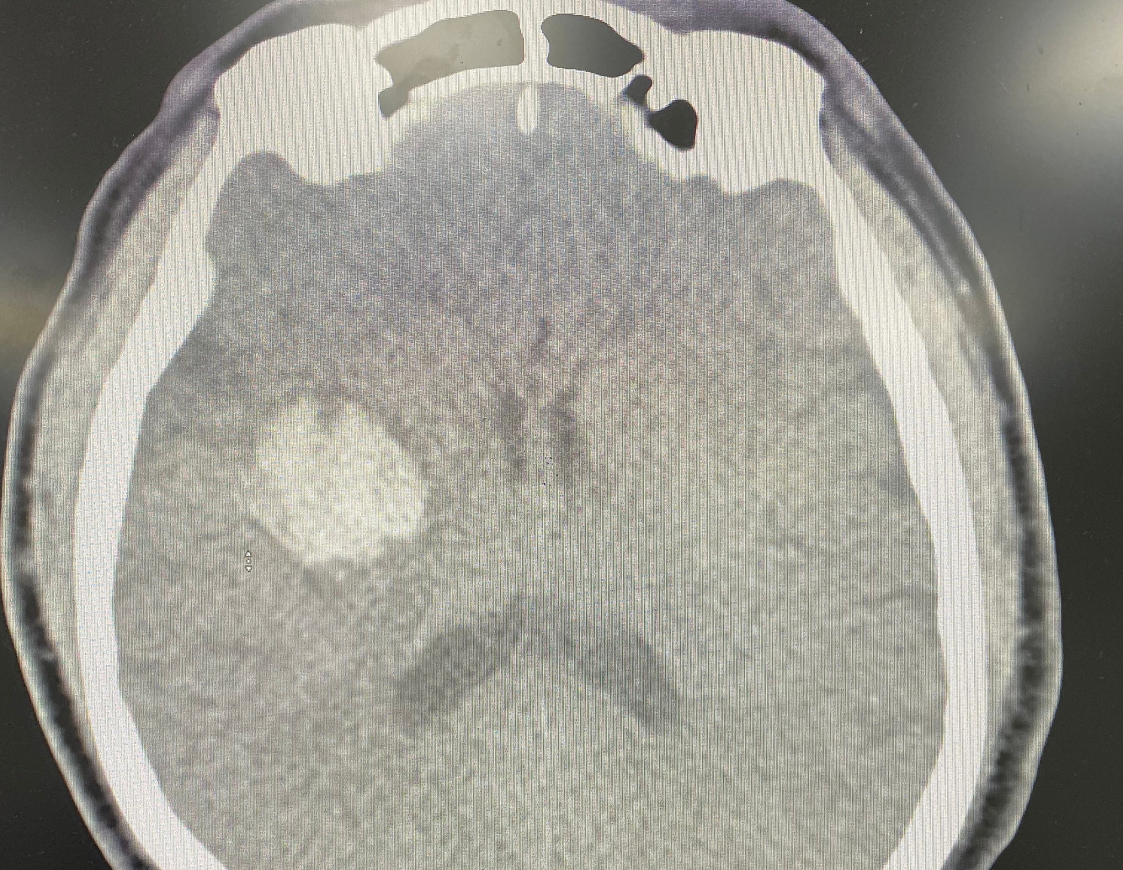

| Hình chụp cắt lớp vi tính sọ não của bệnh nhân. Ảnh: BV 108. |

Sau khi uống thuốc các triệu chứng không cải thiện, thậm chí còn có biểu hiện nặng hơn. Người bệnh vào Khoa Cấp cứu - Bệnh viện Trung ương Quân đội 108 chụp cắt lớp vi tính sọ não dựng hình mạch máu não (CTA), kết quả cho thấy hình ảnh xuất huyết não vùng nhân xám trung ương phải, không có bất thường mạch máu não.